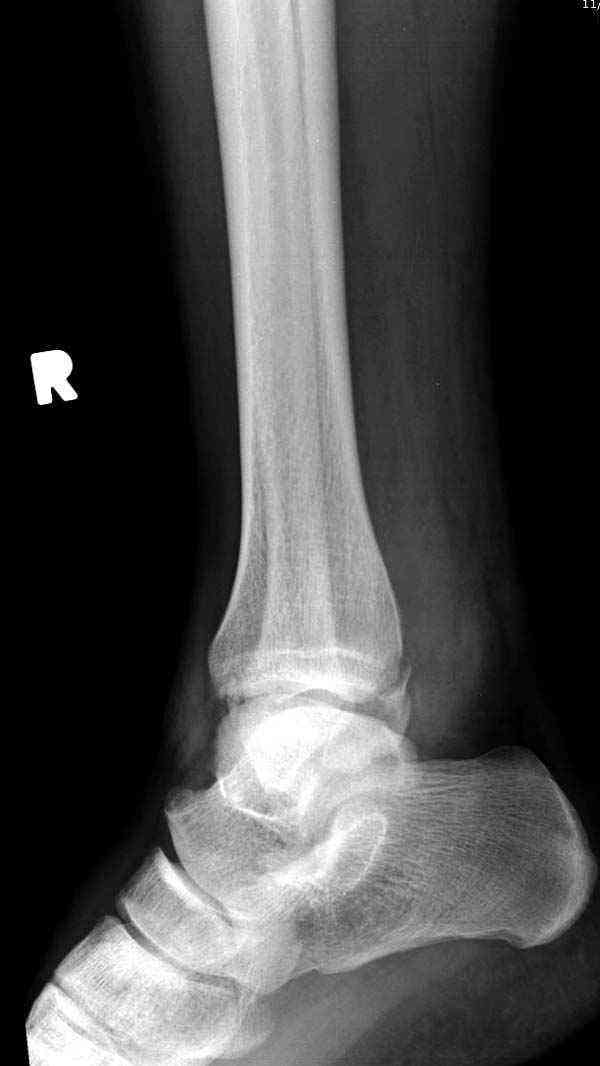

Случай прошлого года:пациентка-молодая ,крупная женщина ,30лет.Травма в начале апреля 2009г-пронационный перелом лодыжек с подвывихом стопы.Ко мне обратилась через 35 дней,прооперирована 22.05.2009г.Внутренняя лодыжка фиксирована по Веберу,наружная реконструктивной пластиной с наложением болта-стяжки.Иммобилизация "сапожок" в течении месяца,затем пригипсовано "стремя".Гипс снят 10.07.2009г

Достаточно быстрое восстановление функции.В октябре 2009г-почувствовала боль,в области рубца над гайкой открылся свищ.На Р-граммах-консолидация переломов и смещение гайки по стяжке.10.11.2009г-конструкции удалены,санация,заживление ран.В настоящее время пациентку ничего не беспокоит.На операции-раскручивание гайки-болталась на конце стяжки.Вопросы:какой механизм раскручивания и что я неправильно сделал?Свои версии:1)в области синдесмоза успела образоваться рубцовая ткань,которая при движении в суставе"пружинила",поскольку голеностопный сустав является спиральным, то и биомеханика подобна кривошипному механизму.2)Реконструктивная пластина не "реконструировалась" по форме лодыжки.Наложил,как есть.То есть подпружинивала сама пластина.Ну,это мои догадки.Что нужно,чтобы избегать впредь таких,пусть и не "страшных"осложнений:Рассверливать через лодыжку область синдесмоза?Ставить шайбу-гровер?Тщательно моделировать пластину?Прилагаю сравнительные снимки-сразу после операции и перед удалением конструкции.

Визуально никаких вопросов по репозиции не было.Да и на основании чего сомнения,что наружная лодыжка не полностью репонирована или прорезалась проволка ???Я не вижу...Снимок после репозиции справа.

Раз ,есть желание посмотреть другую проекцию выкладываю-ну лучшего качества нет...